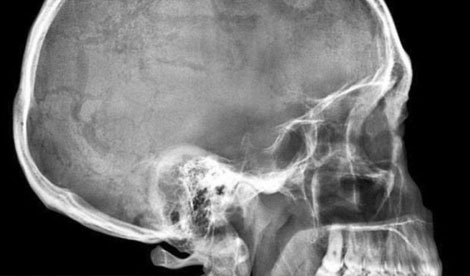

Los médicos encontraron que tenía una bala en la cabeza. La mujer no recordaba haber recibido un disparo.

Ocurrió en Estados Unidos, donde los médicos del Atlanta Medical Center se llevaron una gran sorpresa al encontrar una bala en la parte trasera del cráneo de una mujer que fue para una consulta por dolores de cabeza.

La mujer de 41 años, no recuerda haber sido baleada pero a través de una investigación del FBI, se descubrió que había sido víctima de un tiroteo durante una discusión con su pareja.

Luego de ocho meses de investigación, se determinó que la mujer recibió un disparo dos meses antes de asistir al hospital, luego de una pelea con su pareja. El delito habría ocurrido en la casa de la mujer. Ahora la Policía busca al hombre de 38 años para detenerlo y acusarlo de asalto agravado, agresión agravada y posesión de un arma de fuego de un ex convicto.